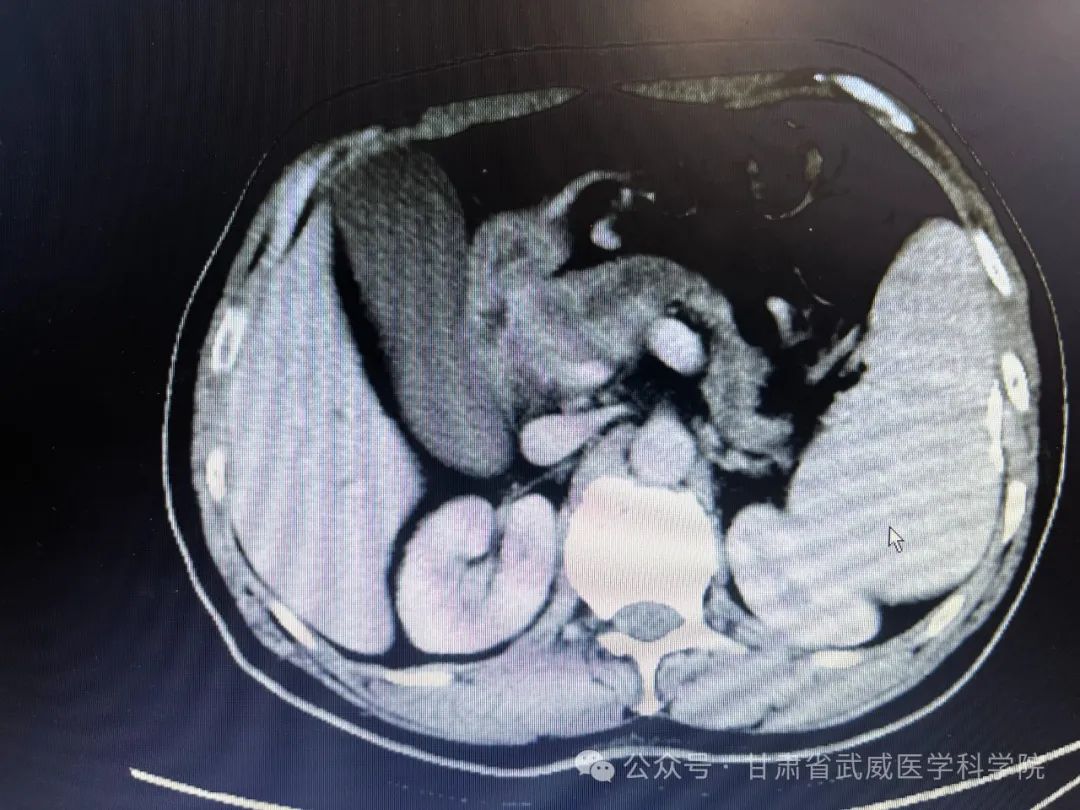

经过5周期化疗后复查腹部CT资料